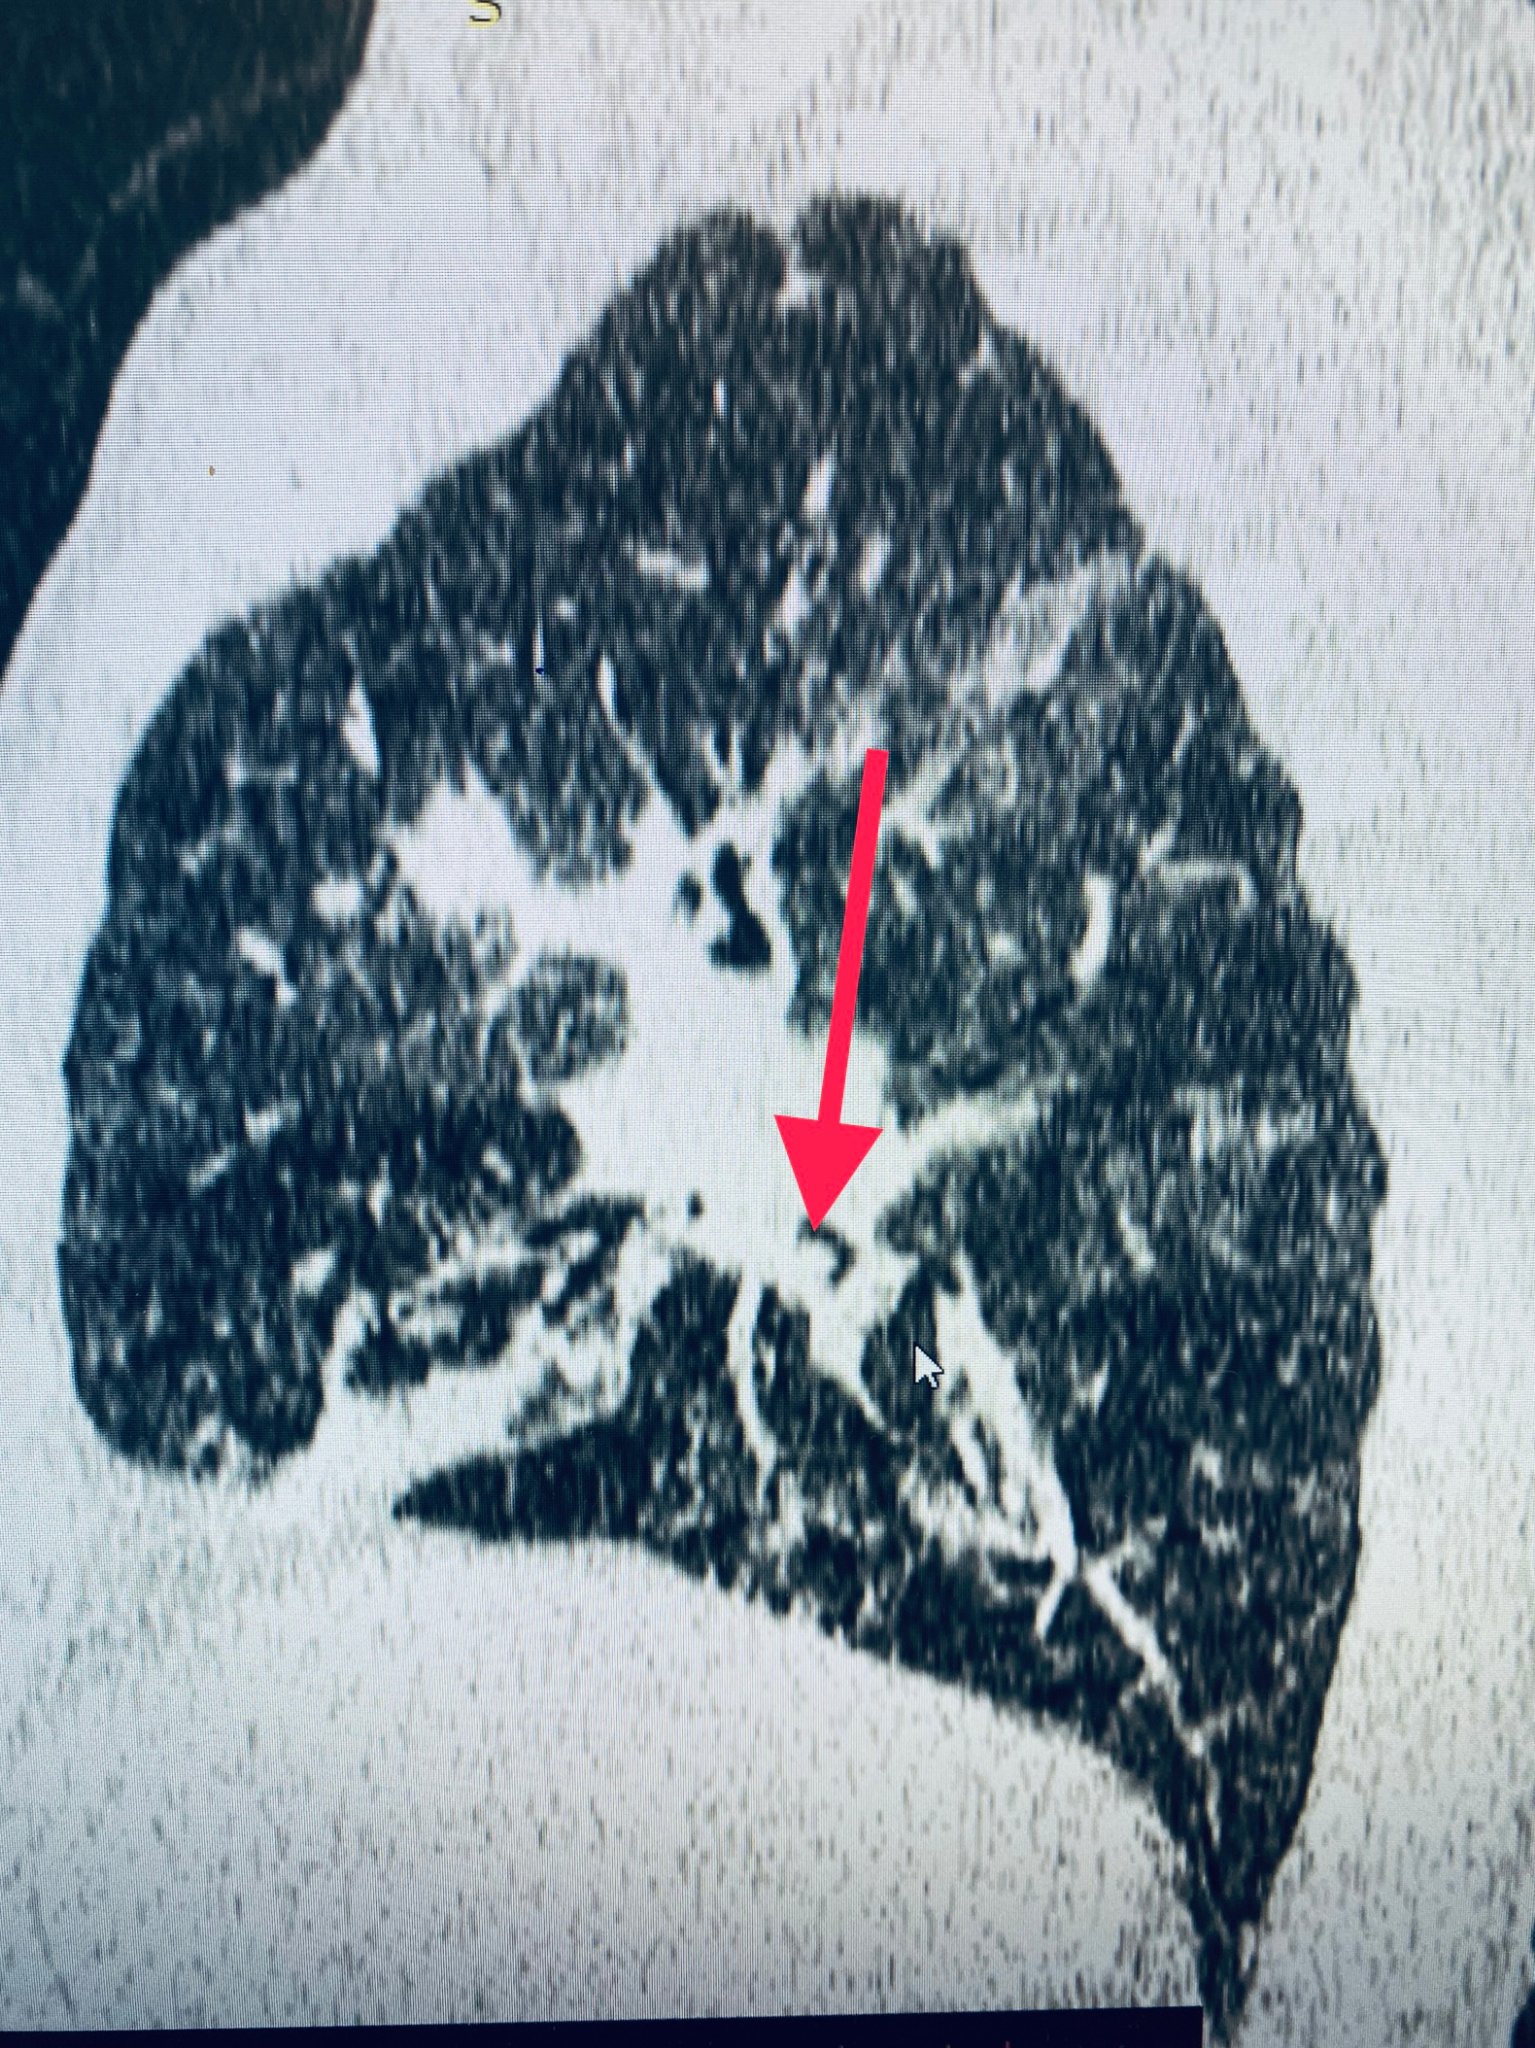

Mjekët në Klinikën e Pulomologjisë kanë kryer një intervenim duke ia larguar një pacienti 84 vjeçar një trup të huaj, i cili i kishte shkaktuar pneumoni të rëndë, si pasojë e pengesës në bronk.

Sipas njoftimit nga ShSKUK, pacienti mashkull, me inicialet M.H., i lindur në vitin 1938, tash është në gjendje të mirë shëndetësore, nën përcjelljen e vazhdueshme të mjekëve, ndërsa pritet të lirohet për në shtëpi brenda javës. /arbresh.info/